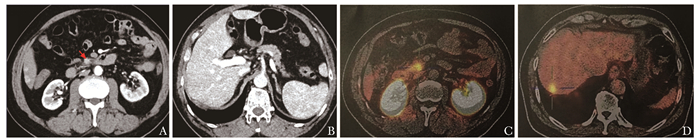

• 摘要: 恶性胰岛素瘤是疑难罕见的神经内分泌肿瘤之一,常合并远处转移,其中以肝转移最常见,预后多不佳。本文报道1例恶性胰岛素瘤多发肝转移病例。患者男性,70岁,因“发作性意识障碍4个月余”入院,监测血糖发现其空腹、餐后及夜间均反复出现低血糖。胰腺灌注CT及肝脏动态增强MRI发现胰头钩突部占位、肝内多发转移灶,经皮肝穿刺活检病理证实为胰岛素瘤。经多学科讨论后,分期行肝内动脉介入栓塞及射频消融治疗,同时联合依维莫司治疗。复查增强CT可见部分肝转移灶缩小。患者规律加餐,血糖逐渐上升并维持在正常水平。本文讨论该病例的临床特征及多学科协作诊疗经过,旨在为恶性胰岛素瘤患者的临床综合诊治提供经验。

Abstract: Malignant insulinoma is a kind of rare and challenging neuroendocrine tumor. It is often accompanied by distant metastasis, among which liver metastasis is most common, and the prognosis is often non-promising. In this paper, we report a case of multiple liver metastases from malignant insulinoma. The patient, a 70-year-old male, was admitted to the hospital due to "episodic consciousness disorder for more than four months." Blood glucose monitoring revealed recurrent hypoglycemia in the early morning, after meals, and at night. Pancreatic perfusion CT and dynamic enhanced MRI of the liver revealed a mass in the uncinate process of the pancreatic head and multiple liver metastases. Percutaneous liver biopsy confirmed the diagnosis of insulinoma. After multidisciplinary discussions, hepatic artery embolization and radiofrequency ablation were performed in stages, in combination with everolimus treatment. Thereafter, the enhanced CT demonstrated that some liver metastases shrank. The patient had regular meals, and the blood sugar gradually increased and remained normal thereafter. This article discusses this case's clinical characteristics and multidisciplinary collaborative diagnosis and treatment, aiming to provide experience for the comprehensive clinical diagnosis and treatment of malignant insulinoma patients.